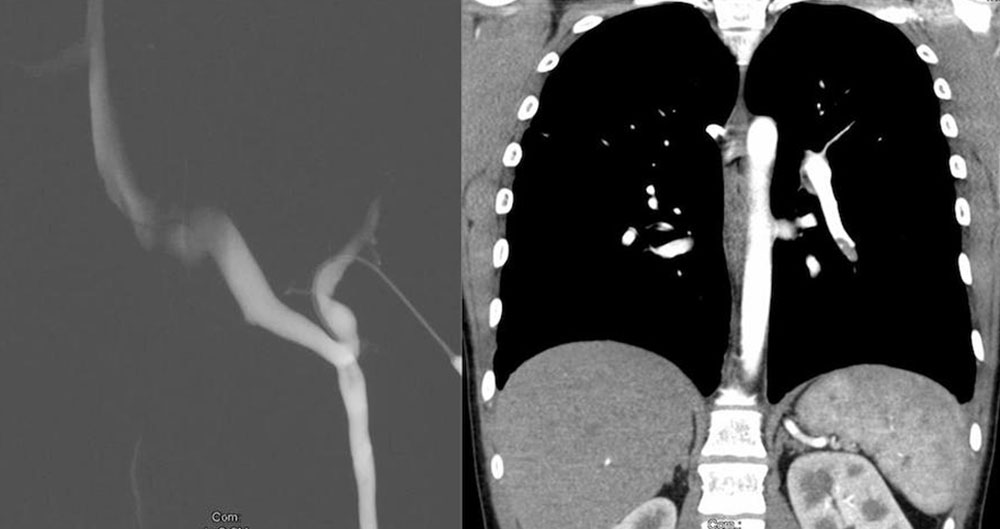

Digitale Substraktionsangiographie (DSA)

Die modernen Schnittbildverfahren (MRT, CT) und insbesondere die MR-Angiographie haben die DSA in der Diagnostik venöser Malformationen verdrängt. Sehr selten ist ihre Anwendung bei Mischformen venöser Malformationen mit ausgeprägten arteriovenösen Fisteln indiziert, wenn entschieden werden muss, ob die arterielle oder venöse Komponente der Fehlbildung Hauptursache der Beschwerden ist. Ansonsten ist sie bei dem Verdacht auf eine venöse Malformation nicht indiziert. Die DSA spielt hingegen bei der Beurteilung einer arteriovenösen Malformation eine relevante Rolle.

Phlebographie

Die aszendierende Phlebographie dient zur Klärung von Aplasien und Dysplasien des tiefen Venensystems, wenn Duplex-Sonographie und MRT keine sichere Beurteilung ermöglichen. Die Indikation ist somit auf sehr spezielle Fragestellungen begrenzt. Die wesentliche Bedeutung der phlebographischen Darstellung durch Direktpunktion liegt in der Durchführung einer Sklerosierung der venösen Malformation.